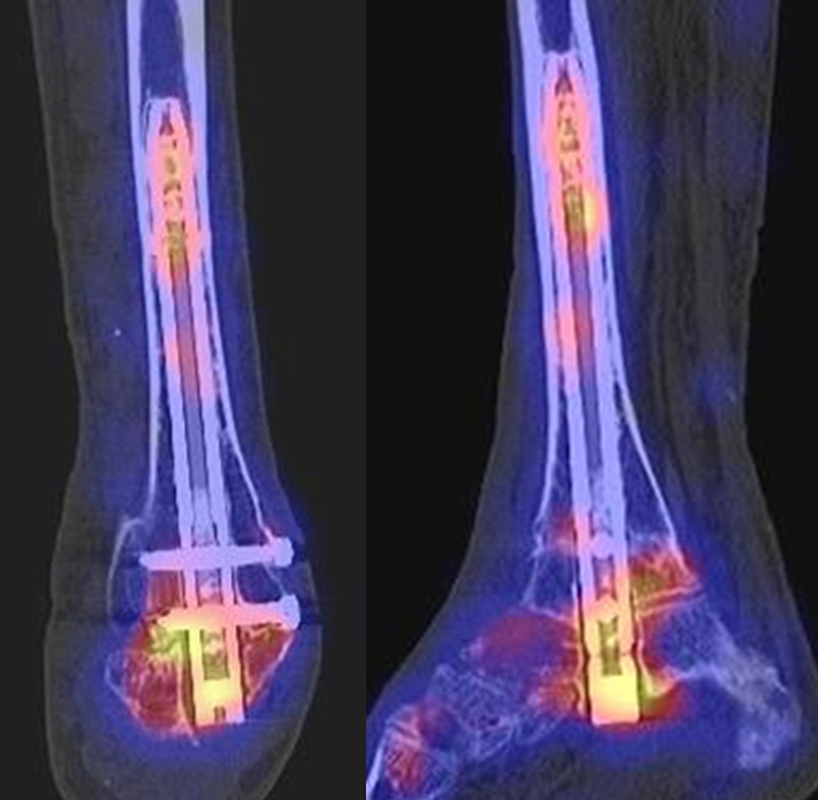

Beispiele für SPECT/CT-Untersuchungen nach OSG-TEP sind in den Abbildungen 6.1. bis 6.3. abgebildet.

Gurbani et al. evaluierten 37 Patienten mit schmerzhaften Sprunggelenkprothesen mit SPECT/CT und korrelierten die Ergebnisse mit klinischen und intraoperativen Befunden. Die SPECT/CT-Ergebnisse korrelierten zu 89,2 % (33/37 Pat.) mit der definitiven Diagnose. 28 Patienten wurden operativ revidiert und der Vergleich der SPECT/CT-Befunde mit den intraoperativen ergab eine Übereinstimmung von 92,9 % (26/28 Pat.). Die SPECT/CT identifizierte in den meisten Fällen aseptische Lockerungen (12/33 Pat.) und Impingement (11/33 Pat.). Seltenere Diagnosen waren Fehlstellungen (4/33 Pat.), Zystenbildungen (2/33 Pat.), subtalare Arthrosen (2/33 Pat.) und Infektionen (2/33 Pat.) 51.

Die Autoren beschreiben einen Fall, der neben einem Fokus am lateralen Malleolus auch eine starke flächige Anreicherung am talaren Prothesen-Knochen-Interface 17 Monate nach TEP-Implantation aufwies, so dass neben dem Verdacht auf ein laterales Impingement auch der Verdacht auf eine Lockerung der talaren Prothesenkomponente geäußert wurde. Intraoperativ bestätigte sich die Lockerung der talaren Prothesenkomponente nicht, sondern nur das laterale Impingement, welches mittels Debridement erfolgreich therapiert wurde 51. Da der Pat. bereits vor der TEP-Implantation eine Triple-Arthrodese erhalten hatte (welche im SPECT/CT unauffällig war), kann eine solche flächige Mehrspeicherung auch als weitgehend asymptomatische Stressreaktion gewertet werden.

Mertens et al. 52 berichten unter Anwendung eines standardisierten Auswerte-Schemas über eine Treffsicherheit von 96 % (Sensitivität 100 %, Spezifität 80 %) des SPECT/CT zur Diagnose der Ursachen für eine schmerzhafte Sprunggelenkprothese (n=24). Der SPECT/CT-Befund führte in 86 % zu einer spezifischen Therapie, welche in 83 % der Fälle zum Therapieerfolg führte.

Eine Analyse von Mason et al. 53 von 14 Patienten mit schmerzhaften Sprunggelenksprothesen, welche mittels SPECT/CT untersucht wurden, fanden in 13/14 Patienten ein SPECT/CT-Korrelat für die Beschwerden, wobei bei 12 Patienten der Fokus talar medial lokalisiert war. 8 Patienten wurden operativ revidiert und der Fokus entsprach einer verminderten bzw. fehlenden ossären Integration der talaren Prothesen-Komponente.